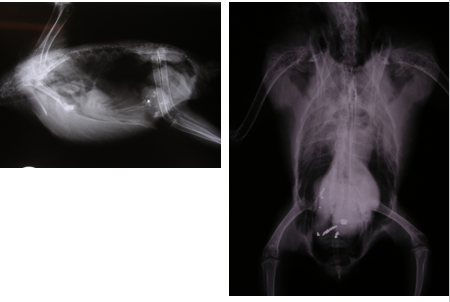

Mr Black, the elderly owner of “Percy” a 3 year old African grey parrot phones the veterinary practice at 5PM after coming home and finding the bird quieter than normal, unable to perch and sitting on the floor and unsteady on its feet.

Percy is on a commercial seed based parrot mix and does not like to eat much fresh fruit and vegetables.

The owners allow the bird free access to the house for 1-2 hours in the morning and evening when they are at home. During the day the bird remains in its large cage, in which it has been housed for 2 years. The owner reports no change in routine or diet. He noticed that Percy seems to have lost his appetite but was not too worried about it because he saw him still drinking frequently. He also has a couple of fish tanks. On initial examination the bird is clearly unsteady on its feet and on handling.

There is a small amount of black/dark green fluid faeces smeared on the underside of the tail feathers and around the cloaca.

Anaesthesia is performed to permit radiography and venous sampling for haematology and biochemistry: Blood sampling (maximum volume approx 2mls (0.5% of body weight))

Radiography: Lateral and ventrodorsal whole body views